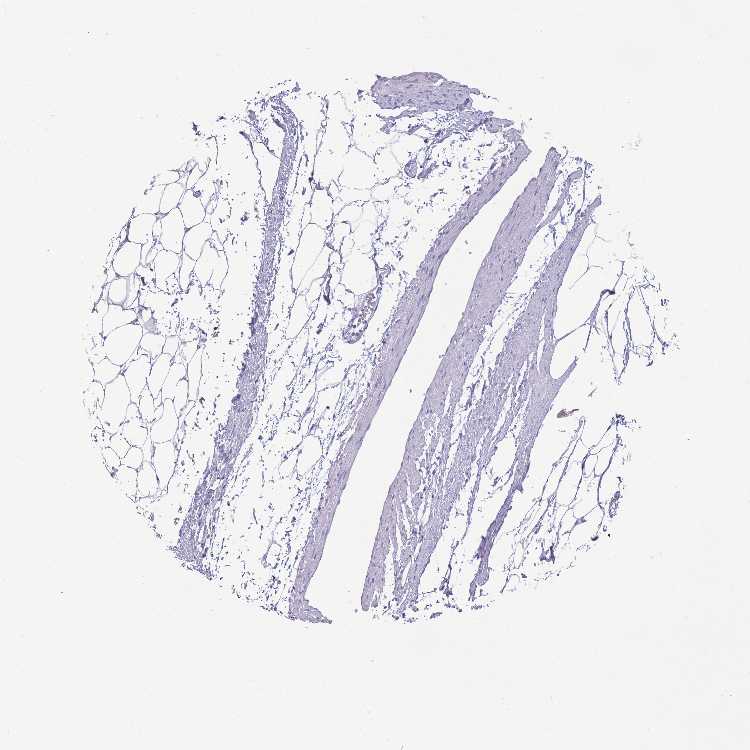

SOFT TISSUE 1 - Antibody stainingi

Antibody staining in the annotated cell types in the current human tissue is reported as not detected, low, medium, or high, based on conventional immunohistochemistry profiling in selected tissues. This score is based on the combination of the staining intensity and fraction of stained cells.

Each image is clickable and will lead to virtual microscopy that enables deeper exploration of all samples and also displays staining intensity scores, fraction scores and subcellular localization as well as patient and tissue information for each sample.

Antibody HPA049524

Fibroblasts Not detected

Peripheral nerve Not detected

SOFT TISSUE 2 - Antibody stainingi